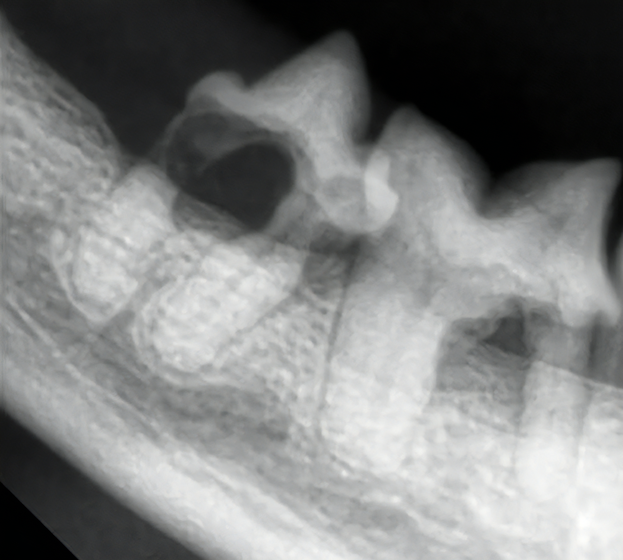

犬の慢性潰瘍性歯周口内炎(2025/11/10)

犬の慢性潰瘍性歯周口内炎は、歯に接する口腔粘膜の持続的な炎症と痛みを特徴する病気です。根本的な病態は解明されていませんが、歯垢の中に存在する細菌に対する過剰な免疫反応が主な原因と考えられています。症状としては、口臭、流涎、歯ぐきや口腔粘膜からの出血や潰瘍、強い痛みなどがよく認められます。徹底的な歯垢除去とその後の継続的なホームケアが治療の要となりますが、清潔な状態が維持できないと歯垢蓄積後の再発も非常に多く、抜歯が最も有効な選択肢となることもあります。採食中やご自宅でのデンタルケアの間などで口に痛みを感じている様子がある場合は、お早めにご相談下さい。